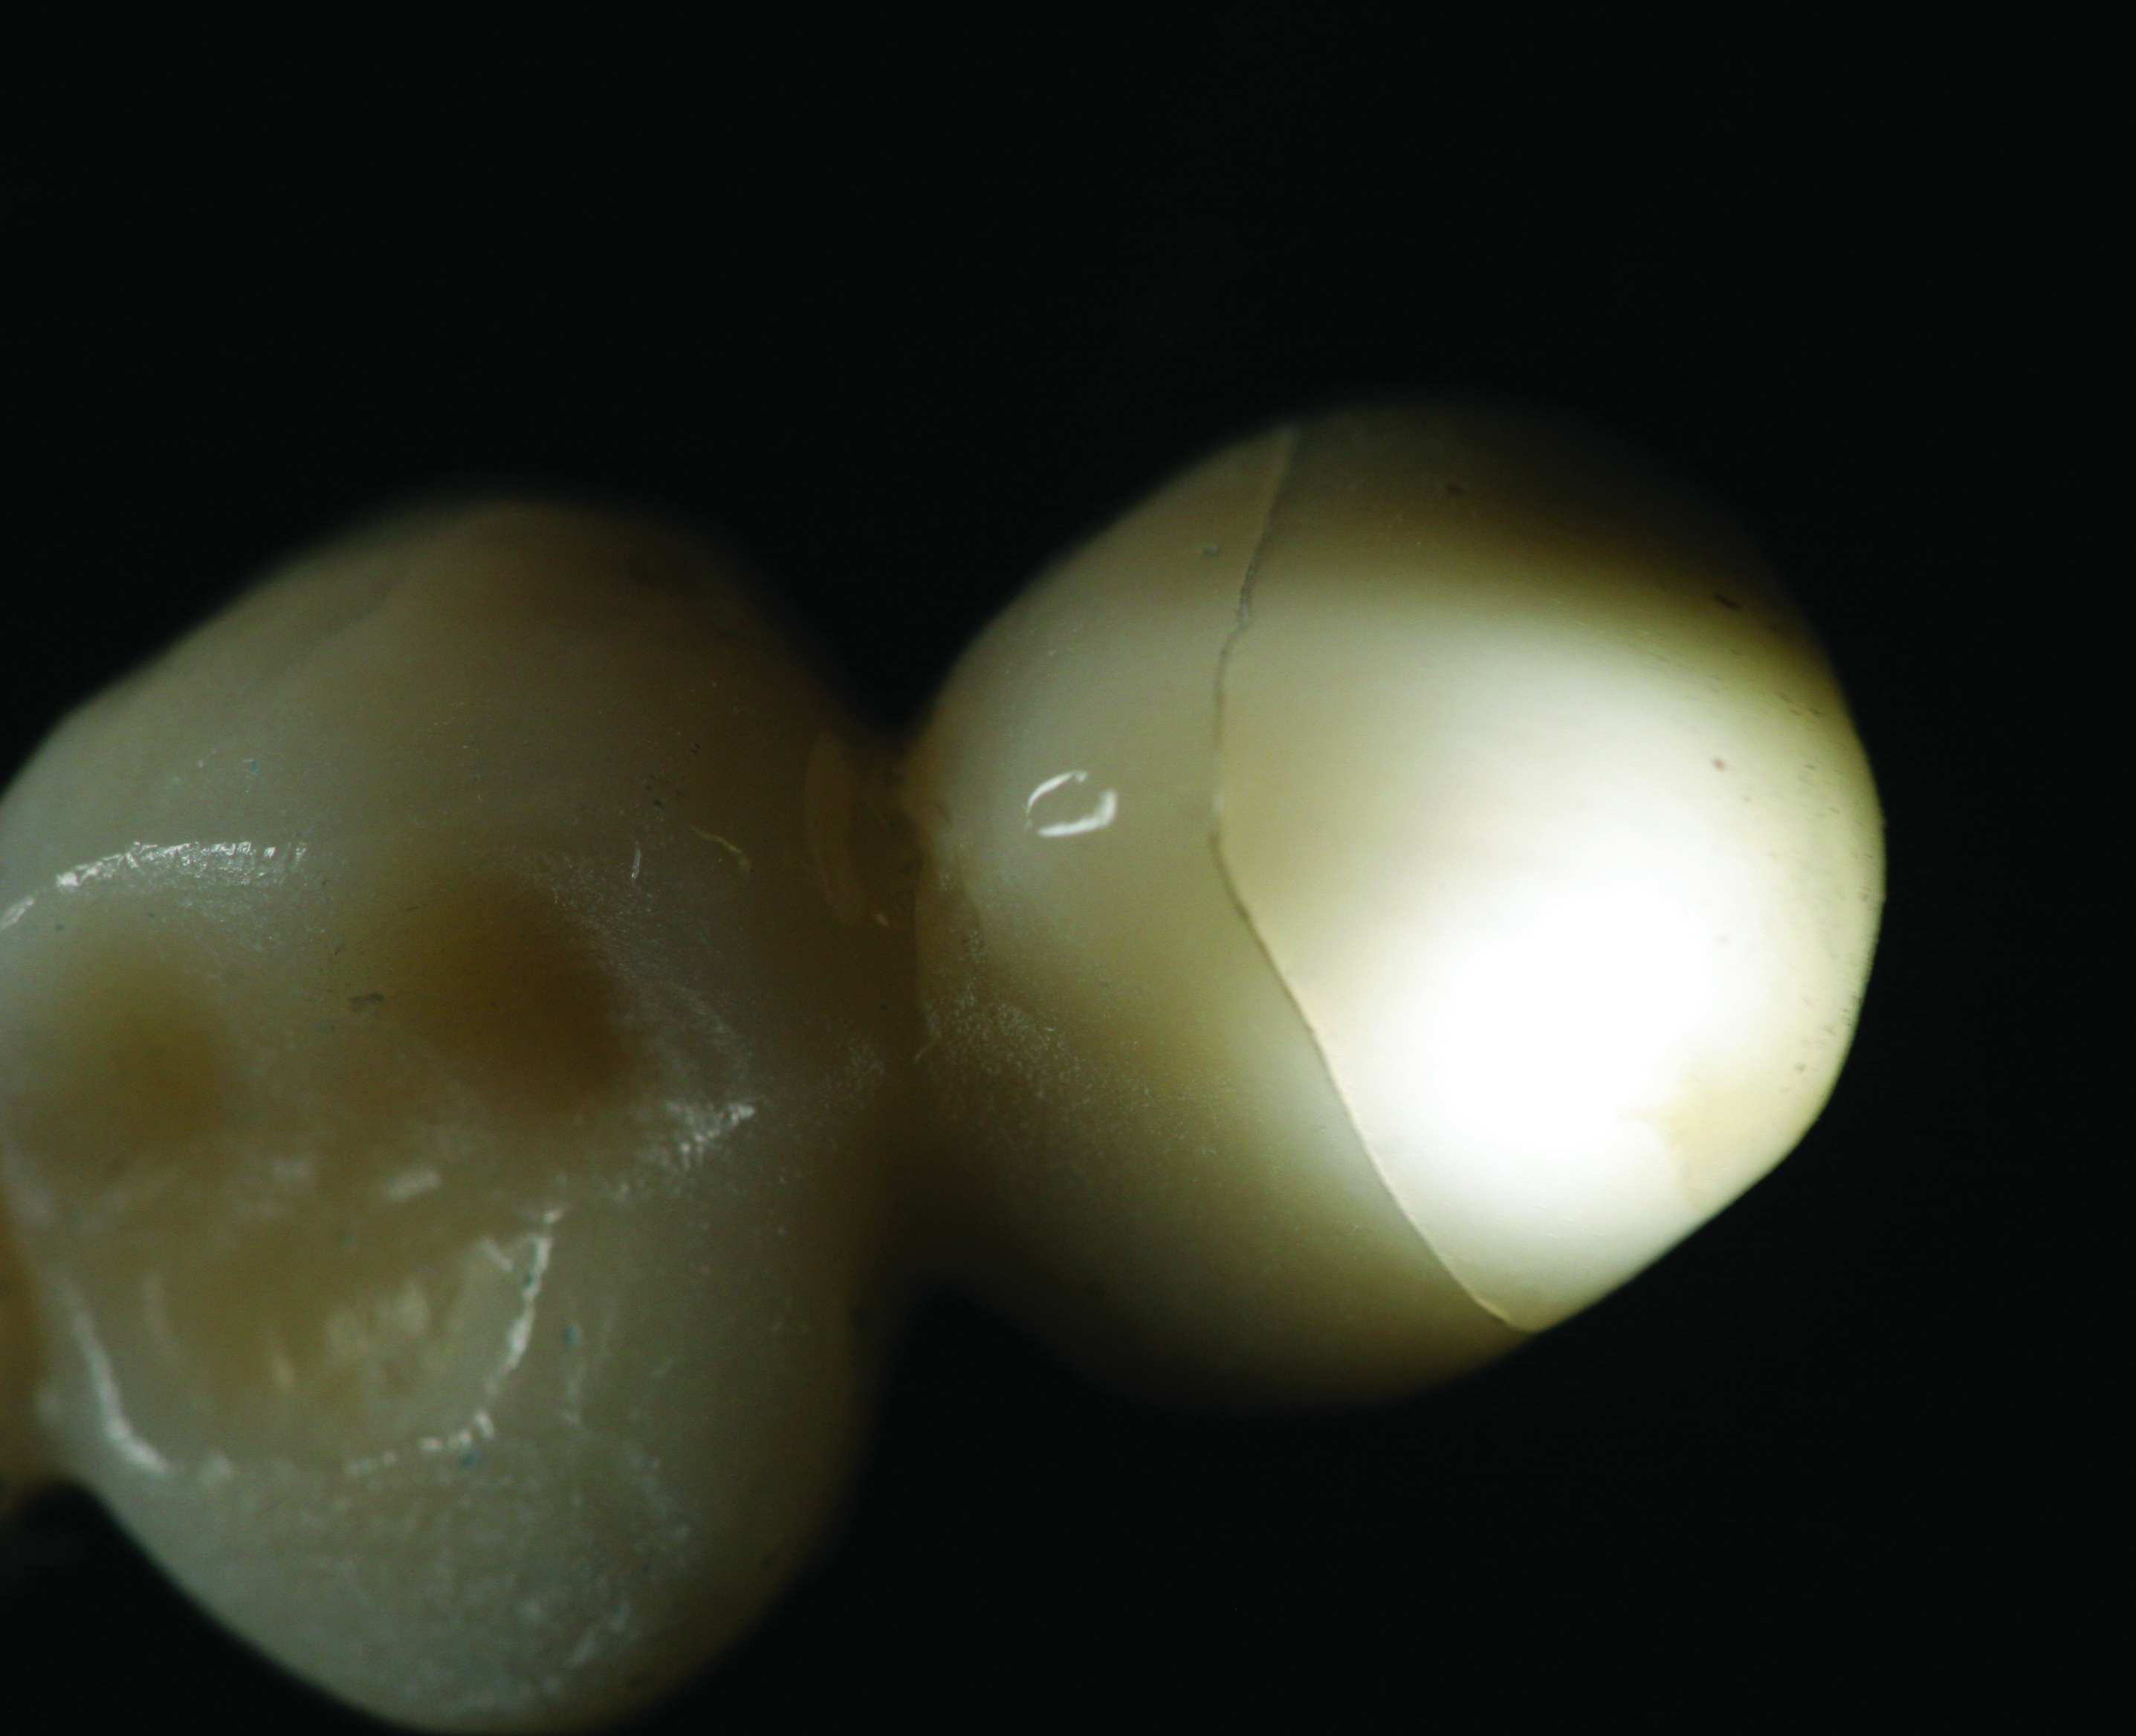

In the anterior, zirconia was first used as a substructure fully veneered with a likely compatible porcelain. Problems began to surface such as delamination of the veneering porcelains. Chipping and bulk fractures of the veneering porcelain without exposure of the zirconia core were occurring2,3 (Figure 2). Causative factors for these failures included a disparity between the coefficients of thermal expansion between the veneering porcelain and the zirconia substructure, low fracture strength of the porcelains, framework design flaws, and sliding contact fatigue.4-6 The bond strength between a feldspathic veneering porcelain can also be affected by the sintering of the feldspathic porcelain itself and the surface treatment of the zirconia substructure.7 For single and multiple anterior units (fixed partial dentures), several fabrication modifications have changed the framework design. The lingual aspect, for example, can be left exposed and milled to full contour while the facial aspect is milled leaving space for veneering porcelains. Other modifications to the fabrication methods have eliminated, for example, the hand-layering of the veneering porcelain and replaced it with a heat-pressed method similar to the press-to-metal technique.3,8 In theory, this approach would seem to have an increase in fracture resistance with a reduction in air voids and with fewer firing cycles.3 Stawarczyk et al9 (referring to this as overpressing) found the fracture loads of PressX Zr Dentine Press Pellets (Ivoclar Vivadent, ivoclarvivadent.us), GC Initial LF (GC America, gcamerica.com), and VITA PM9 (VITA North America, vitanorthamerica.com) were not statistically significant between overpressed and layered porcelain systems. Only IPS e.max® ZirPress (Ivoclar Vivadent) was found to have a significantly higher fracture load than that of the layering porcelains used: ZIROX® (Wieland Dental Systems, wieland-dental.de), GC Initial ZR (GC America), VITA VM9 (VITA North America), or IPS e.max Ceram (Ivoclar Vivadent).

Fig 2. An example of an incomplete fracture of the veneering porcelain to the zirconia substructure.